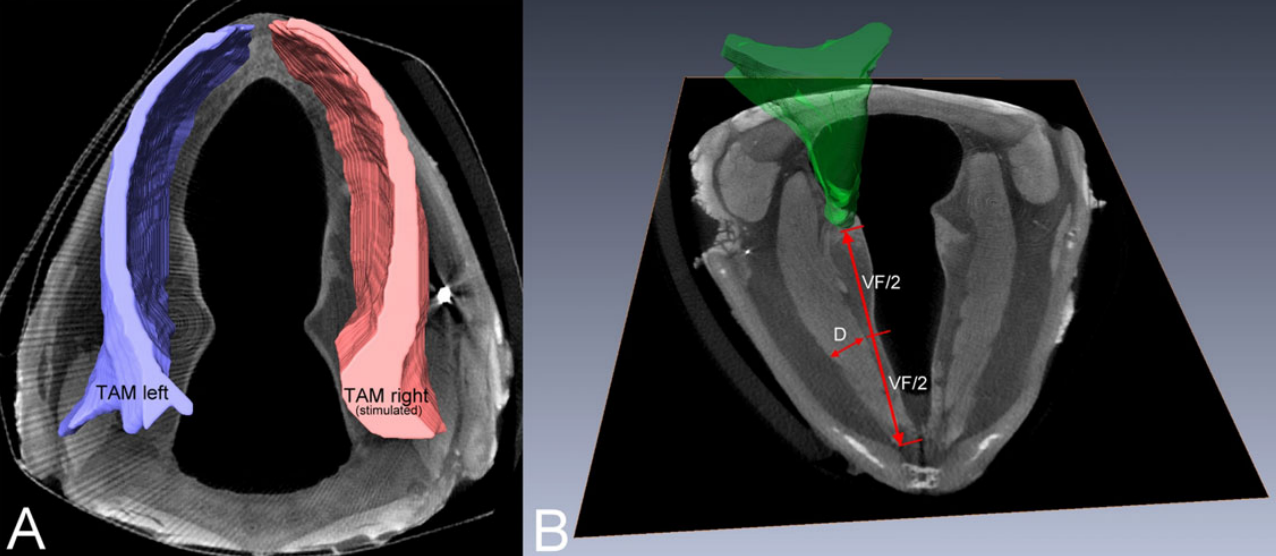

A stimulation electrode was placed unilaterally near the terminal adduction branch of the recurrent laryngeal nerve (RLN) adjacent to the right cricothyroid joint. The electrode was connected to an implant located subcutaneously at the neck region. Predesigned training patterns were automatically delivered by a bidirectional radio frequency link using a programming device and were repeated automatically by the implant every other day over 11 weeks in the awake animal. Outcome parameters comprised volumetric measurements based on three-dimensional reconstructions of the entire thyroarytenoid muscle (TAM), as well as gene expression analyses. We found significant increases of the volumes of the stimulated TAM of 11% and the TAM diameter at the midmembranous parts of the vocal folds of nearly 40%. Based on gene expression, we did not detect a shift of muscle fiber composition. Functional electrical stimulation (FES) of the terminal branches of the RLN is a secure and effective way to reverse the effects of age-related TAM atrophy and to increase volumes of atrophied muscles.

All procedures were carried out as described in a previous study. Briefly, the harvested larynges were placed in 3.75% iodine potassium iodide solution as a contrast agent before being scanned. The images were segmented, 3D reconstructed, and the volume determination of the thyroarytenoid muscle (TAM) was performed with the 3D visualization and analysis software Avizo 9.3.